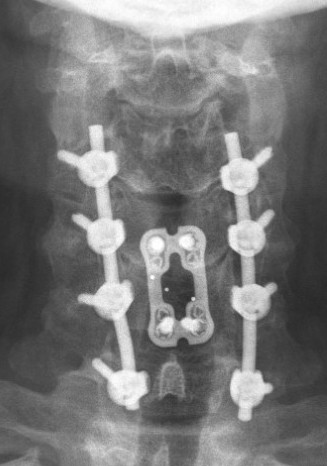

Laminectomy and Fusion

Concept

Posterior decompression is an indirect technique

- requires posterior shifting of the cord in the thecal sac

Indications

Lordotic cervical spine / no kyphotic deformity

Ossification of PLL

Instrumentation

- avoids progressive kyphotic deformity

- lateral mass screws